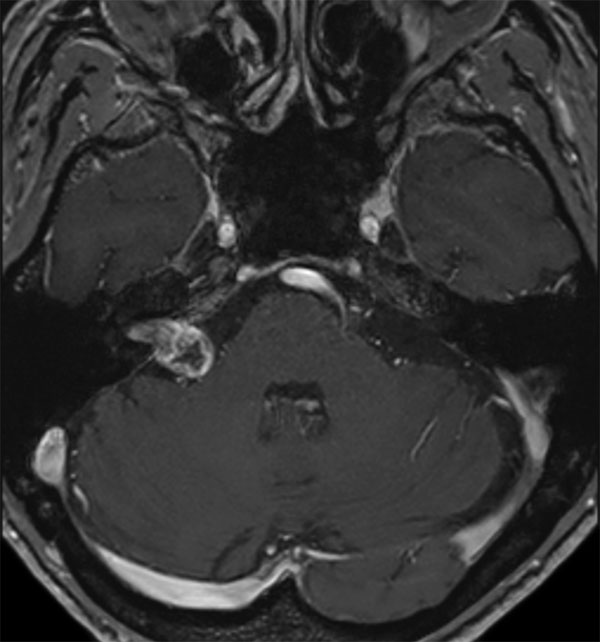

IAC – Acoustic Neuroma

Decreasing hearing of the right side. Buzzing and beating sensation in the right ear. Sometimes pain. Request for MRI of the inner ear without and with contrast agent.